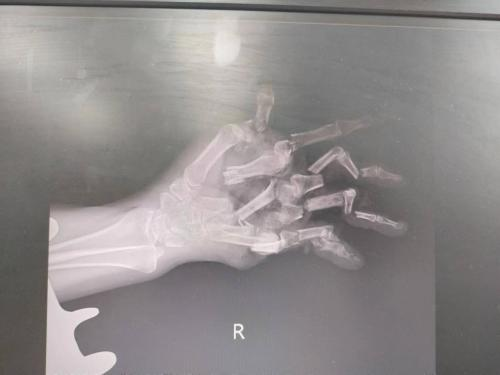

近日,家住寮步的陈大姐用绞肉机绞肉时,不慎发生意外:右手卷进绞肉机,死死卡在机器里无法取出,五根手指及部分手掌已被“绞碎”。

经诊断,陈大姐右手伤情非常严重,环指、小指已被绞碎;右手第1-5掌骨、指骨多发性多段骨折;手部肌腱、血管、神经多处断裂;皮肤软组织碎裂严重。

手足外科团队为了拯救患者右手,先进行彻底清创,对骨折进行固定,恢复骨支架,然后修复断裂肌腱,显微镜下吻合修复血管、神经。

历经7个小时,最终完成修复手术,成功保留右手掌桡侧半及右手拇指、示指、中指,后期通过功能锻炼,手部功能恢复可达到60%以上。